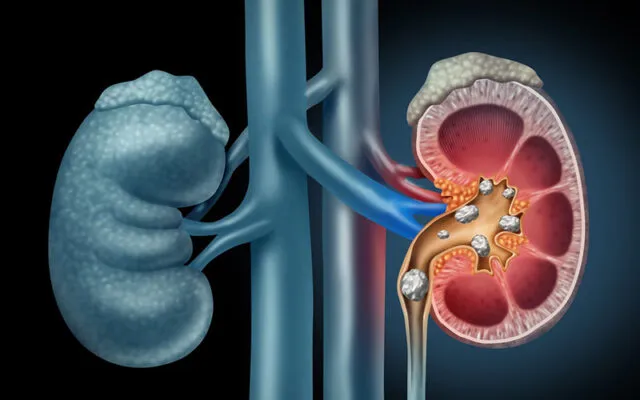

Các phương pháp chữa sỏi thận ở Singapore

Sỏi thận là một bệnh lý phổ biến gây ra nhiều đau đớn và ảnh...

Sỏi tiết niệu: Nguyên nhân và triệu chứng

Bạn có thường xuyên cảm thấy đau quặn ở vùng thắt lưng không? Hay bạn...